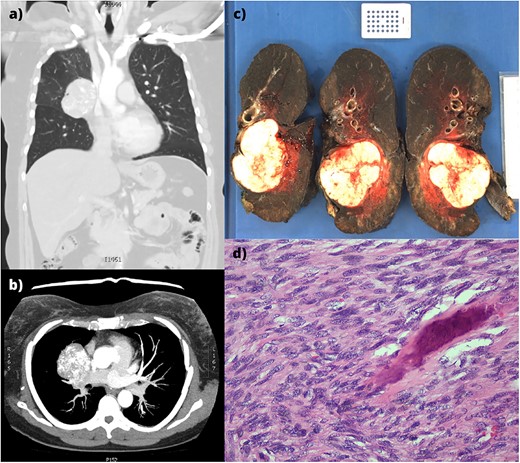

A 58-year-old female with a history of osteosarcoma arising from the right proximal humerus was initially treated with neoadjuvant chemotherapy, resection, and endoprosthetic reconstruction of the humerus, and a pedicled latissimus dorsi flap reconstruction. Four years later, a right middle lobectomy was performed for a metastasis, with histologically clear margins and no nodal involvement. Ten years following the lobectomy, she presented with a new cough. Computed tomography (CT) revealed a right hilar lobulated mass, measuring 7.1 cm × 5.6 cm × 5.9 cm, posteriorly displacing the right main bronchus (Fig. 1a and b). Positron-emission tomography showed significant uptake and an endobronchial ultrasound biopsy confirmed metastatic osteosarcoma.

(a,b) CT imaging showing a large right hilar mass with compression of right main bronchus and superior vena cava. (c) Macroscopic appearance of the right lung containing the tumour and adjacent mediastinal structures. (d) Histopathology of the metastatic osteosarcoma, demonstrating atypical spindle cell morphology.